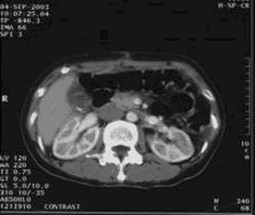

女,49歲。胃體癌晚期,胃竇增厚強(qiáng)化,與周?chē)尺B,腹膜增厚,腹腔廣泛轉(zhuǎn)移,伴大量腹水。放/化療失敗,無(wú)法手術(shù)。治療方案:腹腔灌注今又生2×1012VP/2次/周,共12周,同時(shí)灌注順鉑和5-氟尿嘧啶腹腔,后4周加8次全腹熱療。治療后:第3周,腹水消失;第8周,胃竇、腹膜和網(wǎng)膜變薄,盆腔結(jié)節(jié)明顯變小。后行手術(shù)切除殘余胃腫瘤,術(shù)中探查全腹和盆腔未捫及腫瘤。術(shù)后病檢胃腫瘤內(nèi)未見(jiàn)癌細(xì)胞。

腹腔

盆腔